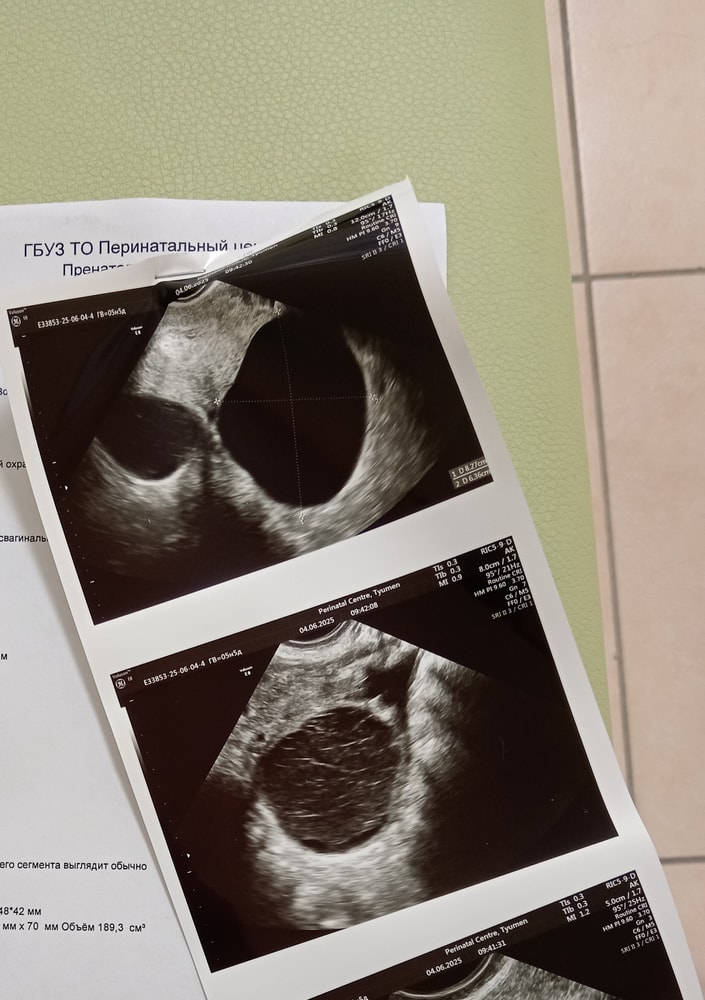

Карина, вот снимок, видимо первые два снимка это правый яичник где киста. Я разглядывала, но выводов не смогла сделать

Но настораживают таки размеры яичника, похоже по ним, что все же киста(

Alinka , снимок приложила в соседний комментарий. До этого особо за кистами не следила, были когда-то функциональные, но мы тогда ещё не пытались забеременеть и поэтому я не обращала на них внимание.

В прошлые пару циклов кист не было.

Alinka , и по поводу размера ПЯ гинеколог сегодня тоже акцентировала внимание. Но я посмотрела фолликулогенез прошлого цикла, там он был ещё больше с ДФ